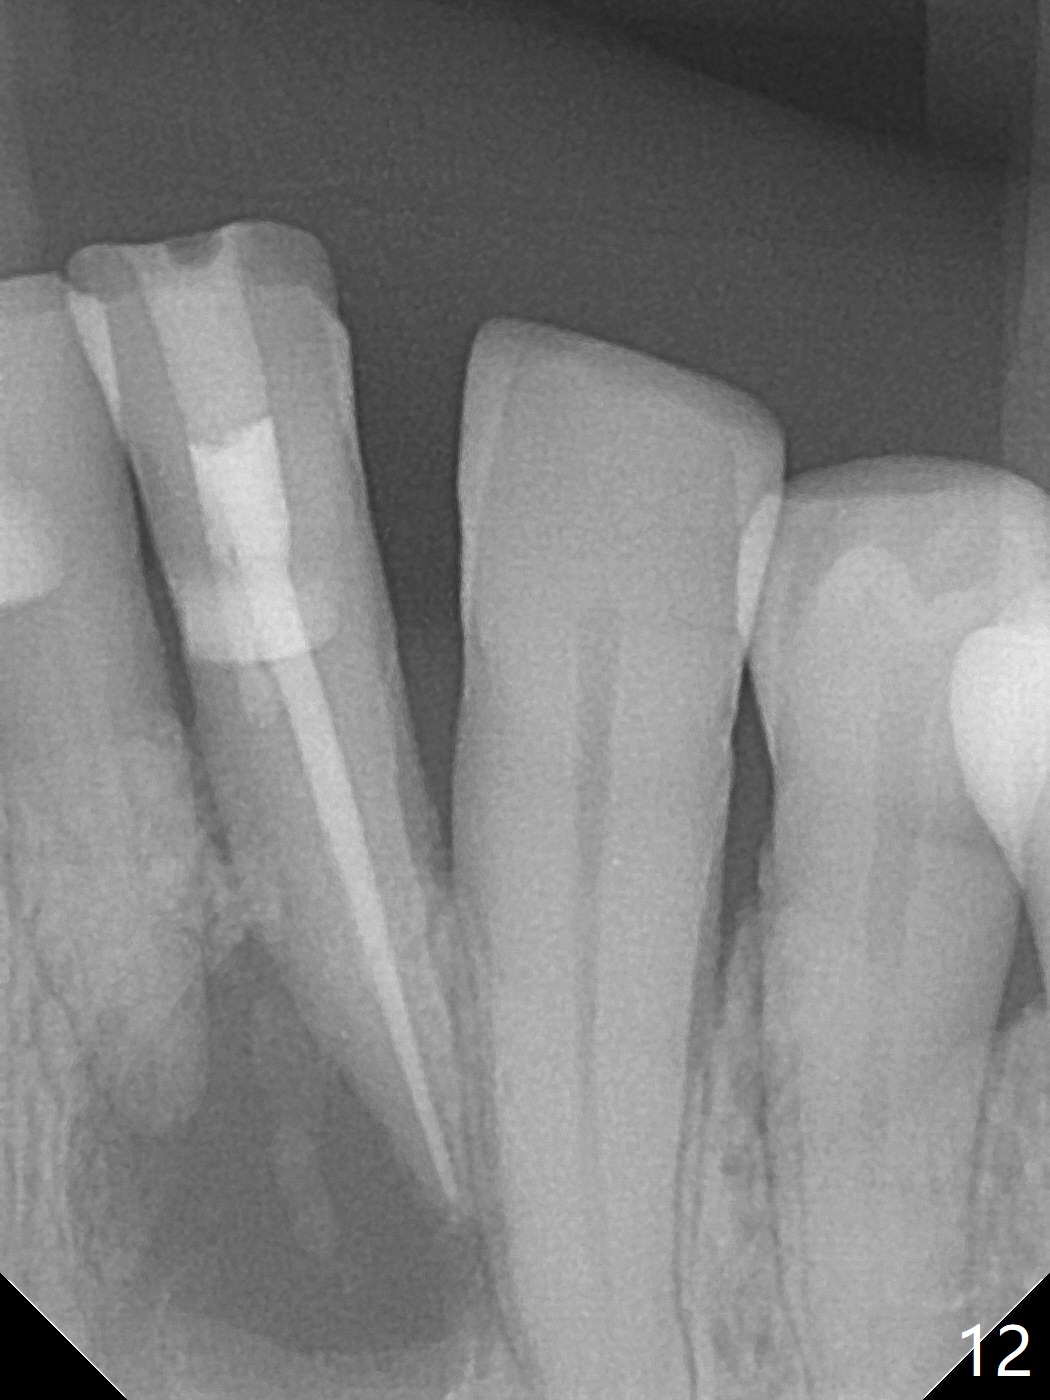

A 73-year-old woman has discomfort associated with #23 four months post Class V composite at #23-25 (Fig.1 C (*: Class V lesions)). Bone loss seems to be more severe lingually, especially at the crest (Fig.2 L). It appears that the apex of the tooth #24 is also in the large apical lesion (Fig.3). Class V composite is apparently continuous with the pulp at #25,24,23 (Fig.5-7). In contrast, Class V defect does not involve the pulp at #26 (Fig.4). If necrosis is confirmed clinically for #23 24 and 25, RCT will be conducted. Due to 7-day Amoxicillin taken for #3 implant, the patient feels that her tongue moves freely, as related to reduction in pain and swelling lingual to #23 (Fig.8 *). Endo ice test shows necrosis of #23 to 25. RCT is initiated at #23 (Fig.9) with buccal and lingual swelling. Endo may have to be at #24 with apicoectomy with PRF. The lingual swelling remains at #23, although there is no pain or purulent discharge 5 and 5.5 months post debridement (Fig.10,11). RCT is finished (Fig.12). Apicoectomy is pending with PRF. Less aggressive curettage will be done at #24 to maintain apical blood supply. Vitality tests have been done without conclusion.